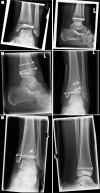

Aims: Understanding the orientation of fracture lines and mechanisms is the essential key to sufficient surgical therapy, but there is still a lack of visualization and teaching methods in traumatology and fracture theory. 3D-printed models offer easy approach to those fractures. This paper explains the use of the teaching possibility with 3-dimensional models of transitional fractures of the ankle.

Methods and results: For generating 3D printable models, already obtained CT data were used and segmented into its different tissues, especially parts concerning the fracture. After the segmentation process, the models were produced with FFF (fused filament fabrication) printing technology. The fracture models then were used for hands-on teaching courses in AO course (Arbeitsgemeinschaft für Osteosynthesefragen) of pediatric traumatology in 2020 in Frankfurt. In the course fracture anatomy with typical fracture lines, approaches, and screw placement could be shown, discussed and practiced.

Conclusion: The study shows the use of 3D-printed teaching models and helps to understand complicated fractures, in this case, transitional fractures of the ankle. The teaching method can be adapted to numerous other use cases.